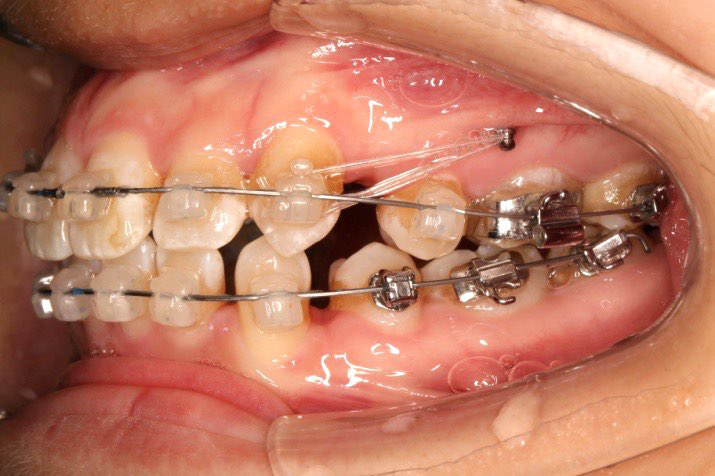

2016.10.31  初戴,0.013cu-niti2017.1.13  上颌加TPA,U56间斜形植入韩国庆北1312-08种植钉,上下0.16cu-niti

2017.02.16  上下0.014*25 cu-niti,50g 拉尖牙远中

2017.04.28

2017.04.28  上0.016*25ss 13、23近远中约5度 v形曲,下0.017*25ss